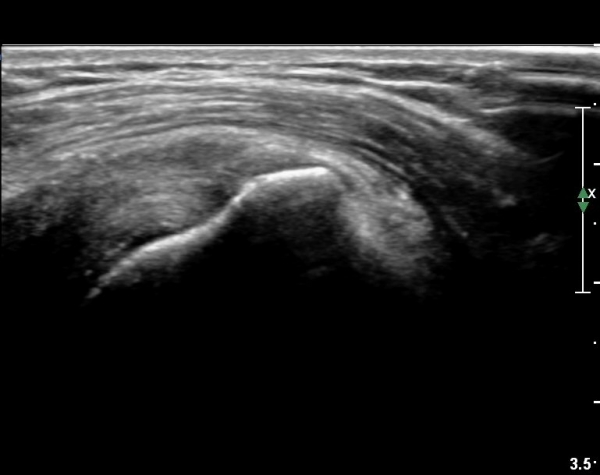

±Ø»ó°Ç Á¶´ã¸é°Ë»ç¿¡¼­ ±Ø»ó°ÇÀÇ ÅðÇ༺º¯È­È­ ºÎºÐÀûÀÎ ÆÄ¿­ÀÌ  °üÂûµÇ¸é ´ë°áÀýÀº

ºñÈĵǾî ÀÖ´Ù(»çÁø 6, 7, 8).